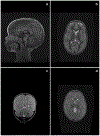

Figure 1:

Brain MRI findings in children with cerebral malaria Panel A shows normal brain volume in a child with cerebral malaria. This sagittal T1 weighted sequence, obtained on a General Electric Signa Ovation 0.35 T scanner, has normal position of the cerebellar tonsils and normal width of the extra-axial fluid spaces including the pre-pontine space. Panel B, obtained from the same patient, is an axial T2 weighted image at the level of the basal ganglia demonstrating normal sulcal outlines with no effacement and normal grey-white matter differentiation. Panel C shows highly increased brain volume in a child with cerebral malaria. This coronal T2 weighted image at the level of the occipital horns of the lateral ventricles demonstrates markedly increased brain volume with generalized sulcal effacement and reduced differentiation of grey and white matter. Panel D, obtained from the same patient, demonstrates sulcal effacement, multifocal areas of reduced grey-white matter differentiation, and partial effacement of the lateral ventricles.